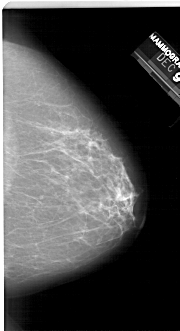

A_1245_1.RIGHT_CC

RIGHT_CC LINES 6271 PIXELS_PER_LINE 3406 BITS_PER_PIXEL 12 RESOLUTION 43.5 NON_OVERLAY